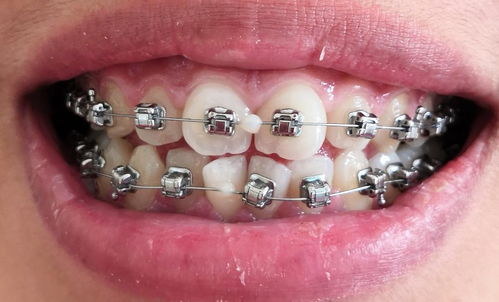

什么是矫治器 矫治器是指用于矫正牙齿牙列不齐的装置,多数是装戴在口腔内的牙齿上,也可以放置在头面部。它必须具有轻便、坚固、耐用、舒适,并且对口腔正常咀嚼和发音等功能影响小等性... 牙齿矫正 丘乐正 616 2023-12-23

戴矫治器时应该注意什么 矫治器是指用于矫正牙齿牙列不齐的装置,多数是装戴在口腔内的牙齿上,也可以放置在头面部。它必须具有轻便、坚固、耐用、舒适,并且对口腔正常咀嚼和发音等功能影响小等性... 牙齿矫正 潭韶敏 1002 2023-12-22

什么叫矫治器 牙列不齐主要用力进行矫治,应用力的装置有多种,最常用的是在口内或口外安放一种装置,这种装置称作矫治器。由于矫治器主要是装置在口内牙齿上或颌面部所以必须便于患者使... 牙齿矫正 鄂昊英 559 2023-11-30